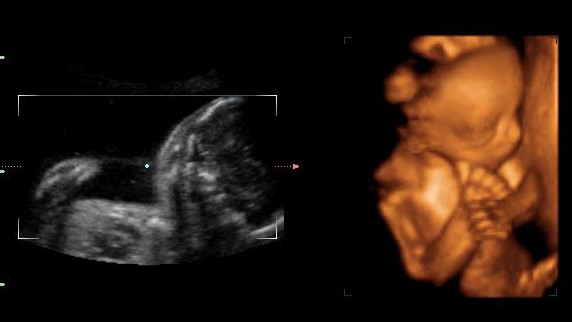

四维胎儿手呈握拳状一般都是男孩吗?

这个说法也是没有科学依据的,宝宝在妈妈的体内会胎动,并且四肢都是可以活动的,宝宝在子宫内手握拳是非常正常的现象,不管是男女宝宝都是这样的,并不能来判断男女。

许多婴儿在妈妈的子宫腔中都是有四肢、手脚有变小的变动,是正常情况,胎儿双手呈握拳状也是正常的。如果有特殊情况,医生一般都会及时通知,也有很大可能是宝宝是检查时处于睡眠状态。也可以根据检测出的各个数据来判断胎儿的发育情况。

男孩一般胎儿四维手呈握拳状